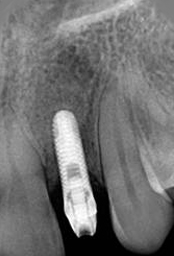

X-ray of Implant

Single Tooth Implant